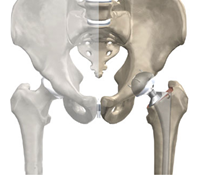

Тотальное эндопротезирование тазобедренного сустава – это операция, когда выполняют удаление поврежденной кости и хряща, с последующей заменой на протез, как головки бедренной кости, так и вертлужной впадины.

Протезы с «бесцементным» типом фиксации покрыты специальным пористым материалом, который позволяет костной ткани пациента по прошествии определенного времени врастать в эти микроскопические поры. Во время операции компоненты эндопротеза – вертлужный компонент (чашка) и бедренный компонент (ножка) впрессовываются в кость для первичной фиксации протеза. Далее, через определенный промежуток времени, костные клетки проникают в специальное пористое покрытие компонентов эндопротеза (кость — это тоже живая ткань), что обеспечивает отличную фиксацию эндопротеза в кости пациента без применения каких-либо дополнительных материалов (без костного цемента).

Зачастую, это пациенты молодого и среднего возраста (в среднем до 65 лет). Это обусловлено тем, что немаловажную роль в процессе фиксации компонентов эндопротеза играет костная ткань, которая должна быть достаточно хорошего качества, плотности и регенеративной активности. Также, данный вид протезирования показан пациентам с диспластическими видами коксартроза (остеоартроз в результате врожденных заболеваний, недоразвития вертлужной впадины и др.).